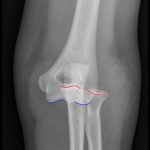

Elbow dislocations are classified by the position of the radio-ulnar joint relative to the humerus.1 Images 1, 2, and 3 show a left posterior elbow dislocation; the radius and ulna are displaced posteriorly with respect to the distal humerus. The lateral view of the elbow most clearly shows this: trochlear notch of the ulna is empty and displaced posteriorly relative to the trochlea. There is no associated fracture. Images 4 and 5 show the elbow status-post reduction, demonstrating proper alignment of the distal humerus with the radius and ulna.